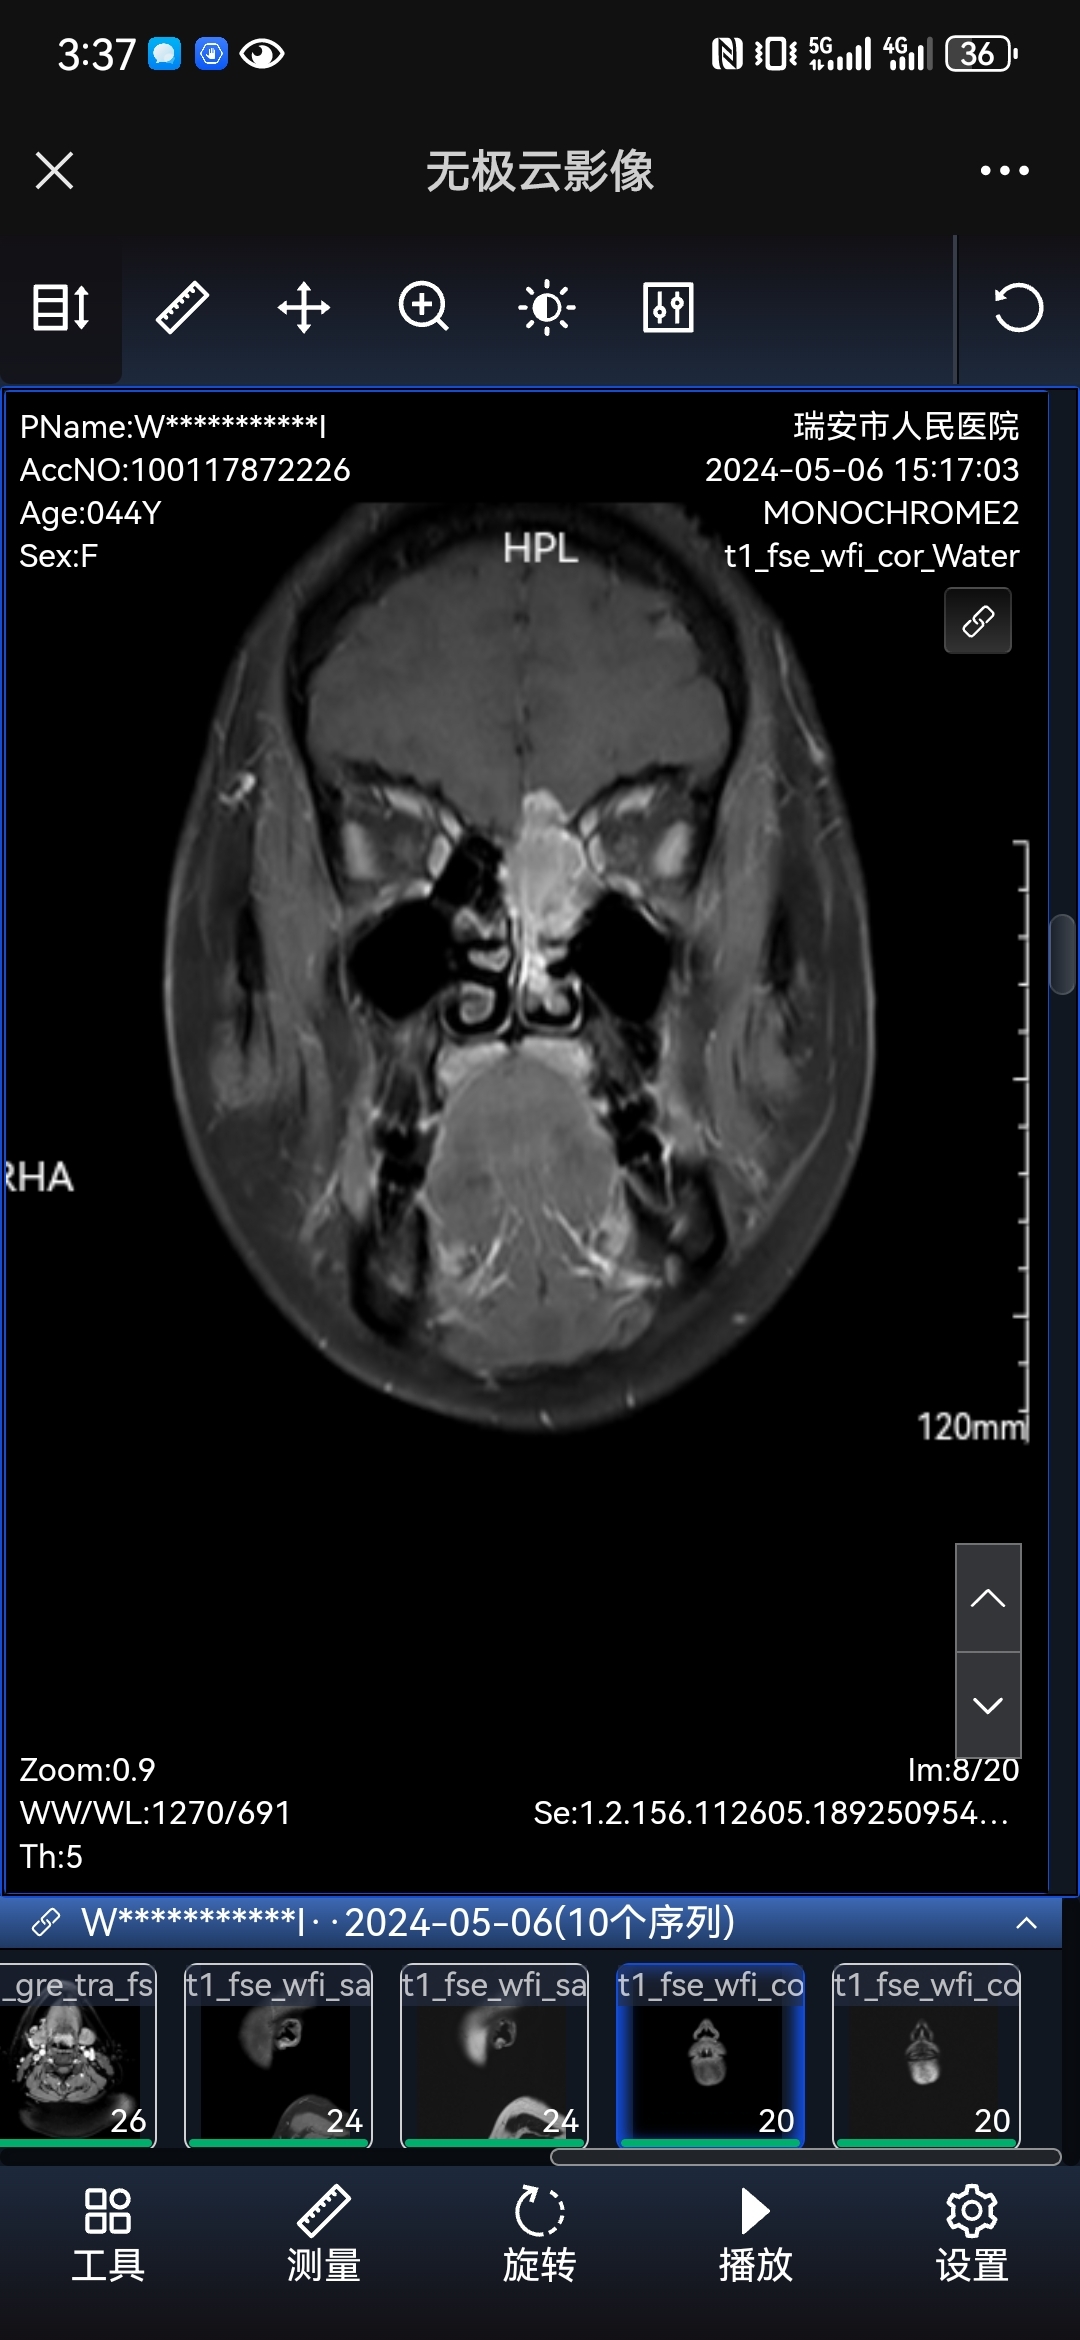

嗅神经母细胞瘤,简称嗅母细胞瘤,是一种罕见的鼻腔鼻窦恶性肿瘤,好发于前颅底筛凹区域的嗅觉黏膜。随着肿瘤生长,嗅母细胞瘤可累及鼻腔、鼻窦各个区域,也常常向上穿透破坏颅底骨质,侵犯颅底及颅内,部分患者就诊时已有淋巴结转移。在疾病早期,患者常常会有鼻塞、鼻出血、嗅觉减退、流涕等不适;而随着疾病的进展及肿瘤对颅底、眼眶、额窦等部位的侵犯,患者也会出现嗅觉丧失、头痛、突眼、复视、溢泪等症状。由于该病较为罕见,患者易被误诊为鼻息肉、内翻性乳头状瘤等较常见的鼻腔肿物,往往需要进行活检或根据手术后病理切片才能最终确诊。目前,手术切除病灶是首选的治疗方法,上海六院耳鼻喉科团队具有丰富的鼻内镜微创手术治疗嗅神经母细胞瘤的经验,尤其在切除侵犯颅底的肿瘤和颅底重建方面独树一帜。下面给大家分享近几年我科诊治的嗅母细胞瘤的部分典型病例。龙X鹏,患者男,23岁患者因“双侧鼻塞3月伴右侧鼻出血,加重1月”至当地医院就诊,同时伴有嗅觉减退、右眼酸痛、溢泪等不适,于外院行鼻咽镜、副鼻窦CT、MRI发现右侧鼻腔肿物,考虑内翻性乳头状瘤可能,为进一步诊治,患者至我院就诊,查体见右侧鼻腔內灰红色息肉样新生物,表面有白色脓性分泌物附着。入院后完善相关检查,我院增强MRI提示病变已侵犯前颅底,根据肿瘤特殊的解剖位置和侵犯行为,结合患者的临床表现,不排除嗅母细胞瘤可能,于是对肿瘤进行了活检,活检病理证实为嗅母细胞瘤。嗅母细胞瘤易侵及颅底,同时邻近眼眶、大血管及神经,要将肿瘤完整切除,手术范围大、时间长、难度高,病灶切除后需要对颅底进行修复和重建,宜采用内镜手术扩大切除肿瘤及筛凹嗅球,术中探查硬膜侵犯情况,根据术中肿瘤范围决定术后是否进行放疗。由于患者既往睡眠打鼾,睡眠监测提示重度夜间低氧血症,生化提示肝功能下降,术前心超提示心尖流出道梗阻,围术期风险高;为了安全、彻底地切除病灶,我科充分发挥六院的多学科协作的优势,在麻醉科、心内科、消化内科的密切配合,以及ICU术后的保驾护航下,患者顺利地接受了鼻内镜手术,病灶被完整切除,术后病理示切缘阴性。尽管手术很成功,患者恢复良好,但是由于肿瘤分期较晚,恶性程度高,因此我们团队又联系放疗科,对术区和引流淋巴结行进一步放疗,以消灭肉眼不可见的癌巢和可能的淋巴结转移灶,减少复发的可能。李X娥,患者女,55岁患者2017年因鼻塞、脓涕等不适就诊于当地医院,行“左侧鼻腔肿物切除术+鼻窦开放术”,术后不适症状基本消失,手术病理提示:嗅神经母细胞瘤。为复查及进一步诊治,患者就诊我科。入院后完善相关检查,结合外院术前影像,考虑肿瘤侵犯前颅底,突破颅内可能,外院手术不够彻底。为切除残余癌灶,我们团队于2017-07-17为患者行鼻内镜下颅底肿瘤切除术+带血管蒂鼻中隔瓣颅底修补术,术中见嗅凹肿瘤残留,送冰冻病理证实,切开硬脑膜,冰冻病理回报肿瘤侵袭,术后患者入ICU监护。后患者恢复可,予以出院,术后定期复诊。2021年,患者因鼻腔异味、脓涕等不适,至当地医院就诊,检查发现鼻腔肿物,活检病理提示小圆细胞,考虑嗅母细胞瘤复发。患者遂至我院就诊,入院后进一步完善相关检查,排除手术禁忌后,我们团队于2021-05-24经鼻内镜切除复发肿瘤,使用颅周骨膜瓣及人工脑膜进行颅底修复,术后入ICU监护,患者恢复良好,术后我院放疗科联合放疗。刘X荣,患者男,49岁患者因“鼻塞半年、流涕2个月”至当地医院就诊,患者自觉嗅觉明显减退,偶有涕中带血和右眼溢泪的症状,查CT及MRI示鼻腔鼻窦肿瘤,侵犯前颅底,活检提示神经内分泌肿瘤(G1)。为进一步诊治,患者就诊我科,门诊拟“鼻腔、鼻窦、颅底恶性肿瘤”收治入院。入院完善相关检查,未发现淋巴结及远处转移证据,外院影像示颅底脑膜增厚,考虑肿瘤侵犯颅内、压迫眼眶。排除手术禁忌后,我们团队于2019-01-21为患者行内镜下颅底病损切除术+颅底修复术,术后入ICU监护,患者恢复良好,予以出院,术后放疗科放疗。半年后患者来院复查,未见复发。王X方,患者女,47岁患者因“左侧涕中带血伴左眼视力下降2月”至当地医院就诊,同时伴有左侧鼻塞、头晕头痛、左眶下及左面部麻木胀痛感,查增强MRI示左侧筛窦占位,伴左咽后、两侧颈部淋巴结肿大,活检病理提示:嗅母细胞瘤。患者遂就诊我院,门诊拟“嗅母细胞瘤”收治入院,入院查体见左侧鼻腔新生物,色红触之易出血,双侧颈部触及肿大固定淋巴结。患者入院后完善相关检查,排除手术禁忌后,我们团队考虑患者目前肿瘤已侵犯左侧眼眶,左眼视力下降明显,遂予甲强龙静滴,弥可保营养神经,应尽早行内镜下鼻腔鼻窦肿瘤切除术+眶减压术,以期改善视力和预后。术后患者恢复良好,一周后行二期手术清扫颅底和颈部淋巴结,病理证实均有肿瘤浸润,出院后予以放化疗。术后3月患者发现颈部出现一肿块,约655cm大小,查PET/CT示鼻腔局部肿瘤复发,已突破左颅底骨质,向上侵犯颅内,左侧面部和颌下多发淋巴结转移,骨转移和肾转移可能,患者和家属有手术愿望,故手术切除颈部皮下肿物和颏下淋巴结,术后继续放疗。陈X能,患者女,37岁患者因“右侧鼻塞2年”入院,鼻塞呈渐进性加重,伴有右侧嗅觉减退,查体见右侧中鼻道粉红色新生物,突入总鼻道。入院后完善相关检查,增强MRI示右侧鼻腔内异常信号灶,考虑内翻性乳头状瘤可能,息肉不除外。因肿物性质不明,排除手术禁忌并与患者充分沟通后,我们团队于2019-07-10为患者进行了鼻内镜下鼻腔鼻窦病损切除术,术中见肿瘤向上源自筛板,向后至蝶筛隐窝,术后病理明确为嗅母细胞瘤。为了彻底切除肿瘤组织,我们于2019-08-14为患者进行了进一步的颅底肿瘤切除术,术中未见可疑组织残留,术后患者入ICU监护。术后恢复可,予以出院,术后联合放射治疗,定期门诊复查随访至今,未见复发。张X,患者男,39岁患者因“鼻塞、脓涕3月”至当地医院就诊,自述有嗅觉减退、右侧面部满胀感,偶有右侧鼻出血等不适,行鼻咽镜检查见右侧鼻腔新生物,取活检未见肿瘤组织。进一步查副鼻窦CT/MRI考虑乳头状瘤可能,遂于该院行鼻内镜手术切除肿物,术后病理示:小细胞恶性肿瘤(高度侵袭性)伴坏死,考虑为嗅神经母细胞瘤。患者携带切片至多家医院病理科会诊,均考虑为嗅母细胞瘤。术后1月左右,患者来到我院就诊,门诊拟“嗅母细胞瘤”收治入院。入院后完善相关检查,未发现淋巴结及远处转移,我院病理科切片会诊示:嗅母细胞瘤伴大片坏死,Hyam’s分级4级,脉管内见癌栓;结合外院术前MRI提示颅底脑膜有增厚,硬脑膜侵犯可能。充分排除手术禁忌后,我们团队于2019-04-17为该患者进行了鼻内镜手术切除颅底残余肿瘤,使用带血管蒂的鼻中隔瓣进行颅底修补重建,术中未见可疑组织残留,术后入ICU监护。患者恢复良好,术后病理未见肿瘤残余,予以出院,密切随访,未行放疗。尽管本例术中已完全切除肿瘤,但由于肿瘤恶性程度高,可能已有早期微小转移,肉眼及影像学检查无法发现。2022年10月,患者因“右颌下无痛性肿物3月余”至当地医院就诊,手术切除肿物后术后病理提示嗅神经母细胞瘤转移。2023年4月患者诉新冠感染后出现右侧鼻塞加重、黄脓涕、涕中带血等症状,于我院就诊。入院查MRI示右侧鼻腔鼻窦嗅母细胞瘤术后复发,侵占下颌窦和右侧眼眶,我们团队为患者行“内镜下颅底病损切除术+鼻内病损切除术+眶减压术”,术后入ICU监护。患者恢复可,术后病理符合复发性嗅母细胞瘤,切缘阴性,予以出院,建议术后放疗。2023年复发术前(上)术后(下)对比图 沈X洋,患者男,32岁患者入院1年前出现反复左侧鼻腔出血,起初未予重视,后症状不改善遂至当地医院就诊,行左侧鼻腔鼻窦肿物切除术,术后病理提示嗅母细胞瘤,术后1月为进一步诊治,就诊我院,门诊拟“嗅母细胞瘤收治入院”。入院后完善相关检查,未发现淋巴结及远处转移证据,结合患者外院术前影像见左侧嗅裂软组织影,考虑为肿瘤残留。排除手术禁忌后,我院鼻科团队于2019-08-14为患者进行了颅底病损切除术+颅底修复术,切除残余癌灶,术后患者入ICU监护。后患者恢复良好,予以出院,定期门诊随访复查,未见复发。王X永,患者男,57岁患者因“鼻塞1年,间断鼻出血半年”至当地医院行CT检查,提示嗅区肿物,后至肿瘤医院行PET/CT检查示:1、右侧鼻腔软组织影,FDG高代谢;2、右侧肿大淋巴结,FDG代谢异常增高,考虑恶性病变可能。患者遂辗转至复旦大学五官科医院就诊,行增强MRI及活检,确诊为嗅神经母细胞瘤,为进一步诊治,患者就诊我科,查体见右侧鼻腔新生物,呈菜团状,表面血管丰富;右侧淋巴结肿大,约鸽蛋大小。入院后完善相关检查,结合外院影像考虑肿瘤可能累及右侧上颌窦、左侧鼻腔,故先行内镜下鼻窦探查术以明确病变范围,制定详细可行的手术方案。排除手术禁忌后,2019-12-06我院耳鼻喉科团队为患者实施了颈部淋巴结清扫术+内镜下颅底病损切除术+带蒂鼻中隔瓣颅底修复术,术顺,术后患者入ICU监护。术后两次鼻腔探查、清理术腔后,患者恢复良好,予以出院。考虑患者肿瘤分期较晚,且已有颈部淋巴结转移,术后予化疗+放疗的联合治疗,后患者定期于我院随访并行鼻腔探查清理术,鼻腔內未见肿瘤复发。2022-08-26复诊时查头颅MRI示颅内多发病灶,考虑肿瘤转移可能,遂转至神经外科拟手术切除病灶以明确病变性质,患者拒绝手术,自动出院。裘X平,患者男,48岁患者因“右侧鼻塞3月”至当地医院就诊,检查见右鼻腔新生物,穿刺活检病理考虑小细胞神经内分泌癌,嗅母细胞瘤不除外。患者遂至我院就诊,查体:右侧鼻腔总鼻道內可见白色乳头状新生物,质软无出血。入院后患者完善相关检查,根据鼻内镜、CT、MRI检查结果及我院病理科会诊意见,患者嗅母细胞瘤(T4N0M0KadishC期)诊断明确,PET/CT及颈部超声未见淋巴结及远处转移证据。排除手术禁忌后,患者于2020-04-08在全麻下行内镜下颅底病损切除术+带蒂鼻中隔瓣颅底修复术,术中见右侧鼻中隔、筛区、蝶骨平台骨质均有肿瘤侵犯,蝶骨平台处脑膜可疑侵犯,术后入ICU监护。术后患者恢复可,予以出院,我们建议患者出院后至放疗科联合放射治疗。陈X华,患者男,46岁患者因“左侧鼻塞4月”至当地医院就诊,偶有左鼻出血、脓涕、溢泪等症状,CT/MRI检查发现筛窦內巨大肿物,向颅内和后鼻道生长,活检病理提示:嗅神经母细胞瘤。为进一步诊治,患者就诊我院。入院后完善相关检查,增强MRI提示肿瘤大小约34mm43mm48mm,累及前颅窝,同时双侧颌下、颈部多发肿大淋巴结,转移可能。我科经过仔细阅片、多学科会诊、讨论之后认为,患者目前嗅母细胞瘤晚期(T4N1M0KadishD期),但无远处转移,仍然可以手术切除肿瘤及肿大淋巴结,术后辅以放化疗以改善预后。排除手术禁忌后,我们于2020-09-24行根治性颈淋巴结清扫+内镜下颅底病损切除术+鼻窦病损切除术,切除绝大部分肉眼可见的肿瘤和淋巴结转移灶,由于病灶切除范围大,采用人工脑膜、大腿阔筋膜和颅骨骨膜瓣进行颅底修复重建,手术耗时13小时,术后患者转入ICU监护。术后患者恢复可,2020-10-09行内镜下鼻窦检查、鼻腔清理术,吸除鼻腔内脓性分泌物和残余纳吸棉,见黏膜瓣血供良好,与周围组织愈合可,未见明显坏死,予以出院,术后放化疗。术前(上)术后(下)对比图:王X敏,患者男,47岁患者因“左侧鼻出血,量大不能自止”至当地医院就诊,诊断为出血性鼻息肉,遂行鼻息肉切除术,术中见肿物与脑膜粘连,颅底骨质破坏,考虑恶性可能,术后病理提示嗅母细胞瘤,患者为求进一步诊治来我院就诊。患者入院后完善相关检查,我院MRI示左侧颅底筛窦区强化影,肿瘤残余可能,未发现远处转移证据。排除手术禁忌后,我们鼻科团队于2021-06-07为患者行鼻内镜下颅底病损切除术,术中见左侧后筛顶部骨质虫噬样改变,局部骨质菲薄,硬膜异常增厚,另蝶骨平台处硬脑膜表面也可见明显肿瘤侵犯,尽可能切除可疑组织后,用双侧鼻中隔瓣进行前颅底修复重建,术后患者入ICU监护。术后患者恢复良好,予以出院,根据术后病理结果和放疗科会诊意见,出院后辅以放射治疗,以期进一步提高患者预后。术前(上)术后(下)对比图: 缪X达,患者男,41岁患者因“左侧鼻塞流涕1年,突发鼻出血1月余”至当地医院就诊,检查发现鼻腔肿物,遂行鼻窦病损切除术,术后病理提示嗅神经母细胞瘤,患者为求进一步诊治就诊我科。入院完善相关检查,未发现肿瘤有远处转移证据,结合外院术前影像见嗅裂、嗅凹及筛孔均有肿瘤侵犯,硬脑膜亦被肿瘤侵及,但肿瘤并未突破至颅内。为了彻底清除肿瘤,在充分排除手术禁忌后,我们团队于2021-08-09为患者进一步行鼻内镜下颅底病损切除术,术中左侧嗅裂见紫红色新生物,触之易出血。术后患者入ICU监护,术后病理回报切缘阴性,患者恢复良好,予以出院。患者出院后于我院规律复查至今,肿瘤未见复发。王X栋,患者男,63岁患者因“右鼻复出血1年余”至当地医院就诊,检查发现右侧鼻腔新生物,活检病理提示:高级别嗅神经母细胞瘤,伴有腺样分化(嗅神经癌),患者为求进一步手术治疗来我院就诊。入院完善相关检查,未发现远处转移证据,CTA示主动脉多发穿透性溃疡形成,请血管外科会诊评估后无绝对手术禁忌,我们团队于2023-06-16为患者进行了鼻内镜下颅底病损切除术,术中见肿瘤累及颅底,切净肿瘤后取右侧鼻中隔瓣修复颅底,冰冻病理回报切缘无肿瘤累及。术后患者入ICU监护,恢复良好,后转入血管外科行胸主动脉支架植入术。患者出院后辅以放疗,定期于我院随访复查,至今未见复发。术前(上)术后(下)对比图: 穆X法,患者男,53岁患者2023年2月因“发现左侧颌下腺肿物”于当地医院行“左颌下腺及肿物切除术”,术后病理示神经内分泌肿瘤(G2),住院期间检查发现双侧鼻腔肿物。追问患者病史,自述双侧鼻塞伴脓涕两年余,伴有鼻出血、溢泪、视力减退、视物模糊等症状,均以左侧为著,嗅觉基本消失。2023年4月外院查PET-CT示:双侧筛窦、鼻腔软组织肿块,侵犯前颅底及副鼻窦,考虑肿瘤性病变;双侧咽后、上颈部多发淋巴结转移。患者为求进一步诊治,门诊拟“双侧鼻腔、鼻窦肿物”收治入院。患者入院后完善相关检查,于2023-05-03局麻下行“鼻内病损切除活检术”,术后病理提示:嗅神经母细胞瘤,2级。因为肿瘤巨大,侵袭颅内、双侧眼眶及各个副鼻窦,且已有颈部淋巴结的转移,手术难度较大,预后不良。我们与患者及家属充分沟通后,决定先予对嗅母细胞瘤敏感的“依托泊苷+顺铂”方案辅助化疗3个疗程,但本例患者化疗效果欠佳。由于患者及家属手术意愿强烈,遂进一步排除手术绝对禁忌,拟分期手术治疗。2023-08-18我们耳鼻喉科团队为患者进行了颈部淋巴结清扫术,经颈部切口外侧入路切除淋巴结转移灶,待患者恢复后再次手术切除鼻内原发灶。2023-09-06,我们为患者进行了鼻腔、鼻窦、颅底病损切除术,术中由于肿瘤占满鼻腔且血供丰富,经鼻处理困难,故选择左侧鼻侧切口入路进行手术,切除颅底、鼻窦、眶内绝大部分肿瘤组织,取人工硬膜覆盖颅底,术后患者入ICU监护,患者恢复可。由于本次手术时间长(10小时),肿瘤血供丰富出血较多,颅内残余肿瘤计划于神经外科二期手术切除。术前(上)术后(下)对比图:嗅神经母细胞瘤,简称嗅母细胞瘤,是一种罕见的鼻腔鼻窦恶性肿瘤,好发于前颅底筛凹区域的嗅觉黏膜。随着肿瘤生长,嗅母细胞瘤可累及鼻腔、鼻窦各个区域,也常常向上穿透破坏颅底骨质,侵犯颅底及颅内,部分患者就诊时已有淋巴结转移。在疾病早期,患者常常会有鼻塞、鼻出血、嗅觉减退、流涕等不适;而随着疾病的进展及肿瘤对颅底、眼眶、额窦等部位的侵犯,患者也会出现嗅觉丧失、头痛、突眼、复视、溢泪等症状。由于该病较为罕见,患者易被误诊为鼻息肉、内翻性乳头状瘤等较常见的鼻腔肿物,往往需要进行活检或根据手术后病理切片才能最终确诊。目前,手术切除病灶是首选的治疗方法,上海六院耳鼻喉科团队具有丰富的鼻内镜微创手术治疗嗅神经母细胞瘤的经验,尤其在切除侵犯颅底的肿瘤和颅底重建方面独树一帜。下面给大家分享近几年我科诊治的嗅母细胞瘤的部分典型病例。龙X鹏,患者男,23岁患者因“双侧鼻塞3月伴右侧鼻出血,加重1月”至当地医院就诊,同时伴有嗅觉减退、右眼酸痛、溢泪等不适,于外院行鼻咽镜、副鼻窦CT、MRI发现右侧鼻腔肿物,考虑内翻性乳头状瘤可能,为进一步诊治,患者至我院就诊,查体见右侧鼻腔內灰红色息肉样新生物,表面有白色脓性分泌物附着。入院后完善相关检查,我院增强MRI提示病变已侵犯前颅底,根据肿瘤特殊的解剖位置和侵犯行为,结合患者的临床表现,不排除嗅母细胞瘤可能,于是对肿瘤进行了活检,活检病理证实为嗅母细胞瘤。嗅母细胞瘤易侵及颅底,同时邻近眼眶、大血管及神经,要将肿瘤完整切除,手术范围大、时间长、难度高,病灶切除后需要对颅底进行修复和重建,宜采用内镜手术扩大切除肿瘤及筛凹嗅球,术中探查硬膜侵犯情况,根据术中肿瘤范围决定术后是否进行放疗。由于患者既往睡眠打鼾,睡眠监测提示重度夜间低氧血症,生化提示肝功能下降,术前心超提示心尖流出道梗阻,围术期风险高;为了安全、彻底地切除病灶,我科充分发挥六院的多学科协作的优势,在麻醉科、心内科、消化内科的密切配合,以及ICU术后的保驾护航下,患者顺利地接受了鼻内镜手术,病灶被完整切除,术后病理示切缘阴性。尽管手术很成功,患者恢复良好,但是由于肿瘤分期较晚,恶性程度高,因此我们团队又联系放疗科,对术区和引流淋巴结行进一步放疗,以消灭肉眼不可见的癌巢和可能的淋巴结转移灶,减少复发的可能。术前术后李X娥,患者女,55岁患者2017年因鼻塞、脓涕等不适就诊于当地医院,行“左侧鼻腔肿物切除术+鼻窦开放术”,术后不适症状基本消失,手术病理提示:嗅神经母细胞瘤。为复查及进一步诊治,患者就诊我科。入院后完善相关检查,结合外院术前影像,考虑肿瘤侵犯前颅底,突破颅内可能,外院手术不够彻底。为切除残余癌灶,我们团队于2017-07-17为患者行鼻内镜下颅底肿瘤切除术+带血管蒂鼻中隔瓣颅底修补术,术中见嗅凹肿瘤残留,送冰冻病理证实,切开硬脑膜,冰冻病理回报肿瘤侵袭,术后患者入ICU监护。后患者恢复可,予以出院,术后定期复诊。2021年,患者因鼻腔异味、脓涕等不适,至当地医院就诊,检查发现鼻腔肿物,活检病理提示小圆细胞,考虑嗅母细胞瘤复发。患者遂至我院就诊,入院后进一步完善相关检查,排除手术禁忌后,我们团队于2021-05-24经鼻内镜切除复发肿瘤,使用颅周骨膜瓣及人工脑膜进行颅底修复,术后入ICU监护,患者恢复良好,术后我院放疗科联合放疗。刘X荣,患者男,49岁患者因“鼻塞半年、流涕2个月”至当地医院就诊,患者自觉嗅觉明显减退,偶有涕中带血和右眼溢泪的症状,查CT及MRI示鼻腔鼻窦肿瘤,侵犯前颅底,活检提示神经内分泌肿瘤(G1)。为进一步诊治,患者就诊我科,门诊拟“鼻腔、鼻窦、颅底恶性肿瘤”收治入院。入院完善相关检查,未发现淋巴结及远处转移证据,外院影像示颅底脑膜增厚,考虑肿瘤侵犯颅内、压迫眼眶。排除手术禁忌后,我们团队于2019-01-21为患者行内镜下颅底病损切除术+颅底修复术,术后入ICU监护,患者恢复良好,予以出院,术后放疗科放疗。半年后患者来院复查,未见复发。王X方,患者女,47岁患者因“左侧涕中带血伴左眼视力下降2月”至当地医院就诊,同时伴有左侧鼻塞、头晕头痛、左眶下及左面部麻木胀痛感,查增强MRI示左侧筛窦占位,伴左咽后、两侧颈部淋巴结肿大,活检病理提示:嗅母细胞瘤。患者遂就诊我院,门诊拟“嗅母细胞瘤”收治入院,入院查体见左侧鼻腔新生物,色红触之易出血,双侧颈部触及肿大固定淋巴结。患者入院后完善相关检查,排除手术禁忌后,我们团队考虑患者目前肿瘤已侵犯左侧眼眶,左眼视力下降明显,遂予甲强龙静滴,弥可保营养神经,应尽早行内镜下鼻腔鼻窦肿瘤切除术+眶减压术,以期改善视力和预后。术后患者恢复良好,一周后行二期手术清扫颅底和颈部淋巴结,病理证实均有肿瘤浸润,出院后予以放化疗。术后3月患者发现颈部出现一肿块,约655cm大小,查PET/CT示鼻腔局部肿瘤复发,已突破左颅底骨质,向上侵犯颅内,左侧面部和颌下多发淋巴结转移,骨转移和肾转移可能,患者和家属有手术愿望,故手术切除颈部皮下肿物和颏下淋巴结,术后继续放疗。陈X能,患者女,37岁患者因“右侧鼻塞2年”入院,鼻塞呈渐进性加重,伴有右侧嗅觉减退,查体见右侧中鼻道粉红色新生物,突入总鼻道。入院后完善相关检查,增强MRI示右侧鼻腔内异常信号灶,考虑内翻性乳头状瘤可能,息肉不除外。因肿物性质不明,排除手术禁忌并与患者充分沟通后,我们团队于2019-07-10为患者进行了鼻内镜下鼻腔鼻窦病损切除术,术中见肿瘤向上源自筛板,向后至蝶筛隐窝,术后病理明确为嗅母细胞瘤。为了彻底切除肿瘤组织,我们于2019-08-14为患者进行了进一步的颅底肿瘤切除术,术中未见可疑组织残留,术后患者入ICU监护。术后恢复可,予以出院,术后联合放射治疗,定期门诊复查随访至今,未见复发。张X,患者男,39岁患者因“鼻塞、脓涕3月”至当地医院就诊,自述有嗅觉减退、右侧面部满胀感,偶有右侧鼻出血等不适,行鼻咽镜检查见右侧鼻腔新生物,取活检未见肿瘤组织。进一步查副鼻窦CT/MRI考虑乳头状瘤可能,遂于该院行鼻内镜手术切除肿物,术后病理示:小细胞恶性肿瘤(高度侵袭性)伴坏死,考虑为嗅神经母细胞瘤。患者携带切片至多家医院病理科会诊,均考虑为嗅母细胞瘤。术后1月左右,患者来到我院就诊,门诊拟“嗅母细胞瘤”收治入院。入院后完善相关检查,未发现淋巴结及远处转移,我院病理科切片会诊示:嗅母细胞瘤伴大片坏死,Hyam’s分级4级,脉管内见癌栓;结合外院术前MRI提示颅底脑膜有增厚,硬脑膜侵犯可能。充分排除手术禁忌后,我们团队于2019-04-17为该患者进行了鼻内镜手术切除颅底残余肿瘤,使用带血管蒂的鼻中隔瓣进行颅底修补重建,术中未见可疑组织残留,术后入ICU监护。患者恢复良好,术后病理未见肿瘤残余,予以出院,密切随访,未行放疗。尽管本例术中已完全切除肿瘤,但由于肿瘤恶性程度高,可能已有早期微小转移,肉眼及影像学检查无法发现。2022年10月,患者因“右颌下无痛性肿物3月余”至当地医院就诊,手术切除肿物后术后病理提示嗅神经母细胞瘤转移。2023年4月患者诉新冠感染后出现右侧鼻塞加重、黄脓涕、涕中带血等症状,于我院就诊。入院查MRI示右侧鼻腔鼻窦嗅母细胞瘤术后复发,侵占下颌窦和右侧眼眶,我们团队为患者行“内镜下颅底病损切除术+鼻内病损切除术+眶减压术”,术后入ICU监护。患者恢复可,术后病理符合复发性嗅母细胞瘤,切缘阴性,予以出院,建议术后放疗。2023年复发术前(上)术后(下)对比图 沈X洋,患者男,32岁患者入院1年前出现反复左侧鼻腔出血,起初未予重视,后症状不改善遂至当地医院就诊,行左侧鼻腔鼻窦肿物切除术,术后病理提示嗅母细胞瘤,术后1月为进一步诊治,就诊我院,门诊拟“嗅母细胞瘤收治入院”。入院后完善相关检查,未发现淋巴结及远处转移证据,结合患者外院术前影像见左侧嗅裂软组织影,考虑为肿瘤残留。排除手术禁忌后,我院鼻科团队于2019-08-14为患者进行了颅底病损切除术+颅底修复术,切除残余癌灶,术后患者入ICU监护。后患者恢复良好,予以出院,定期门诊随访复查,未见复发。王X永,患者男,57岁患者因“鼻塞1年,间断鼻出血半年”至当地医院行CT检查,提示嗅区肿物,后至肿瘤医院行PET/CT检查示:1、右侧鼻腔软组织影,FDG高代谢;2、右侧肿大淋巴结,FDG代谢异常增高,考虑恶性病变可能。患者遂辗转至复旦大学五官科医院就诊,行增强MRI及活检,确诊为嗅神经母细胞瘤,为进一步诊治,患者就诊我科,查体见右侧鼻腔新生物,呈菜团状,表面血管丰富;右侧淋巴结肿大,约鸽蛋大小。入院后完善相关检查,结合外院影像考虑肿瘤可能累及右侧上颌窦、左侧鼻腔,故先行内镜下鼻窦探查术以明确病变范围,制定详细可行的手术方案。排除手术禁忌后,2019-12-06我院耳鼻喉科团队为患者实施了颈部淋巴结清扫术+内镜下颅底病损切除术+带蒂鼻中隔瓣颅底修复术,术顺,术后患者入ICU监护。术后两次鼻腔探查、清理术腔后,患者恢复良好,予以出院。考虑患者肿瘤分期较晚,且已有颈部淋巴结转移,术后予化疗+放疗的联合治疗,后患者定期于我院随访并行鼻腔探查清理术,鼻腔內未见肿瘤复发。2022-08-26复诊时查头颅MRI示颅内多发病灶,考虑肿瘤转移可能,遂转至神经外科拟手术切除病灶以明确病变性质,患者拒绝手术,自动出院。裘X平,患者男,48岁患者因“右侧鼻塞3月”至当地医院就诊,检查见右鼻腔新生物,穿刺活检病理考虑小细胞神经内分泌癌,嗅母细胞瘤不除外。患者遂至我院就诊,查体:右侧鼻腔总鼻道內可见白色乳头状新生物,质软无出血。入院后患者完善相关检查,根据鼻内镜、CT、MRI检查结果及我院病理科会诊意见,患者嗅母细胞瘤(T4N0M0KadishC期)诊断明确,PET/CT及颈部超声未见淋巴结及远处转移证据。排除手术禁忌后,患者于2020-04-08在全麻下行内镜下颅底病损切除术+带蒂鼻中隔瓣颅底修复术,术中见右侧鼻中隔、筛区、蝶骨平台骨质均有肿瘤侵犯,蝶骨平台处脑膜可疑侵犯,术后入ICU监护。术后患者恢复可,予以出院,我们建议患者出院后至放疗科联合放射治疗。陈X华,患者男,46岁患者因“左侧鼻塞4月”至当地医院就诊,偶有左鼻出血、脓涕、溢泪等症状,CT/MRI检查发现筛窦內巨大肿物,向颅内和后鼻道生长,活检病理提示:嗅神经母细胞瘤。为进一步诊治,患者就诊我院。入院后完善相关检查,增强MRI提示肿瘤大小约34mm43mm48mm,累及前颅窝,同时双侧颌下、颈部多发肿大淋巴结,转移可能。我科经过仔细阅片、多学科会诊、讨论之后认为,患者目前嗅母细胞瘤晚期(T4N1M0KadishD期),但无远处转移,仍然可以手术切除肿瘤及肿大淋巴结,术后辅以放化疗以改善预后。排除手术禁忌后,我们于2020-09-24行根治性颈淋巴结清扫+内镜下颅底病损切除术+鼻窦病损切除术,切除绝大部分肉眼可见的肿瘤和淋巴结转移灶,由于病灶切除范围大,采用人工脑膜、大腿阔筋膜和颅骨骨膜瓣进行颅底修复重建,手术耗时13小时,术后患者转入ICU监护。术后患者恢复可,2020-10-09行内镜下鼻窦检查、鼻腔清理术,吸除鼻腔内脓性分泌物和残余纳吸棉,见黏膜瓣血供良好,与周围组织愈合可,未见明显坏死,予以出院,术后放化疗。术前(上)术后(下)对比图: 王X敏,患者男,47岁患者因“左侧鼻出血,量大不能自止”至当地医院就诊,诊断为出血性鼻息肉,遂行鼻息肉切除术,术中见肿物与脑膜粘连,颅底骨质破坏,考虑恶性可能,术后病理提示嗅母细胞瘤,患者为求进一步诊治来我院就诊。患者入院后完善相关检查,我院MRI示左侧颅底筛窦区强化影,肿瘤残余可能,未发现远处转移证据。排除手术禁忌后,我们鼻科团队于2021-06-07为患者行鼻内镜下颅底病损切除术,术中见左侧后筛顶部骨质虫噬样改变,局部骨质菲薄,硬膜异常增厚,另蝶骨平台处硬脑膜表面也可见明显肿瘤侵犯,尽可能切除可疑组织后,用双侧鼻中隔瓣进行前颅底修复重建,术后患者入ICU监护。术后患者恢复良好,予以出院,根据术后病理结果和放疗科会诊意见,出院后辅以放射治疗,以期进一步提高患者预后。术前(上)术后(下)对比图: 缪X达,患者男,41岁患者因“左侧鼻塞流涕1年,突发鼻出血1月余”至当地医院就诊,检查发现鼻腔肿物,遂行鼻窦病损切除术,术后病理提示嗅神经母细胞瘤,患者为求进一步诊治就诊我科。入院完善相关检查,未发现肿瘤有远处转移证据,结合外院术前影像见嗅裂、嗅凹及筛孔均有肿瘤侵犯,硬脑膜亦被肿瘤侵及,但肿瘤并未突破至颅内。为了彻底清除肿瘤,在充分排除手术禁忌后,我们团队于2021-08-09为患者进一步行鼻内镜下颅底病损切除术,术中左侧嗅裂见紫红色新生物,触之易出血。术后患者入ICU监护,术后病理回报切缘阴性,患者恢复良好,予以出院。患者出院后于我院规律复查至今,肿瘤未见复发。王X栋,患者男,63岁患者因“右鼻复出血1年余”至当地医院就诊,检查发现右侧鼻腔新生物,活检病理提示:高级别嗅神经母细胞瘤,伴有腺样分化(嗅神经癌),患者为求进一步手术治疗来我院就诊。入院完善相关检查,未发现远处转移证据,CTA示主动脉多发穿透性溃疡形成,请血管外科会诊评估后无绝对手术禁忌,我们团队于2023-06-16为患者进行了鼻内镜下颅底病损切除术,术中见肿瘤累及颅底,切净肿瘤后取右侧鼻中隔瓣修复颅底,冰冻病理回报切缘无肿瘤累及。术后患者入ICU监护,恢复良好,后转入血管外科行胸主动脉支架植入术。患者出院后辅以放疗,定期于我院随访复查,至今未见复发。术前(上)术后(下)对比图: 穆X法,患者男,53岁患者2023年2月因“发现左侧颌下腺肿物”于当地医院行“左颌下腺及肿物切除术”,术后病理示神经内分泌肿瘤(G2),住院期间检查发现双侧鼻腔肿物。追问患者病史,自述双侧鼻塞伴脓涕两年余,伴有鼻出血、溢泪、视力减退、视物模糊等症状,均以左侧为著,嗅觉基本消失。2023年4月外院查PET-CT示:双侧筛窦、鼻腔软组织肿块,侵犯前颅底及副鼻窦,考虑肿瘤性病变;双侧咽后、上颈部多发淋巴结转移。患者为求进一步诊治,门诊拟“双侧鼻腔、鼻窦肿物”收治入院。患者入院后完善相关检查,于2023-05-03局麻下行“鼻内病损切除活检术”,术后病理提示:嗅神经母细胞瘤,2级。因为肿瘤巨大,侵袭颅内、双侧眼眶及各个副鼻窦,且已有颈部淋巴结的转移,手术难度较大,预后不良。我们与患者及家属充分沟通后,决定先予对嗅母细胞瘤敏感的“依托泊苷+顺铂”方案辅助化疗3个疗程,但本例患者化疗效果欠佳。由于患者及家属手术意愿强烈,遂进一步排除手术绝对禁忌,拟分期手术治疗。2023-08-18我们耳鼻喉科团队为患者进行了颈部淋巴结清扫术,经颈部切口外侧入路切除淋巴结转移灶,待患者恢复后再次手术切除鼻内原发灶。2023-09-06,我们为患者进行了鼻腔、鼻窦、颅底病损切除术,术中由于肿瘤占满鼻腔且血供丰富,经鼻处理困难,故选择左侧鼻侧切口入路进行手术,切除颅底、鼻窦、眶内绝大部分肿瘤组织,取人工硬膜覆盖颅底,术后患者入ICU监护,患者恢复可。由于本次手术时间长(10小时),肿瘤血供丰富出血较多,颅内残余肿瘤计划于神经外科二期手术切除。术前(上)术后(下)对比图: